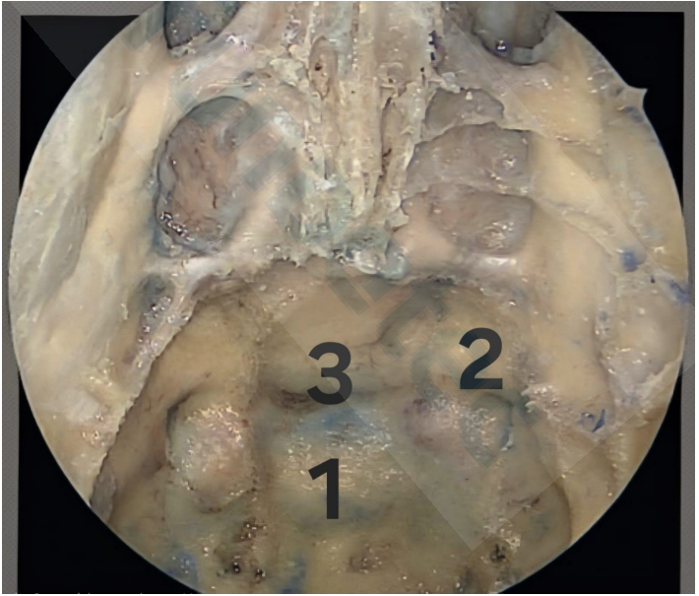

Na Figura abaixo, há uma dissecção cadavérica demonstrando a visão endoscópica endonasal da fossa anterior, muito comum nos acessos à região selar.

Assinale a alternativa que identifica, correta e respectivamente, as estruturas 1, 2 e 3.